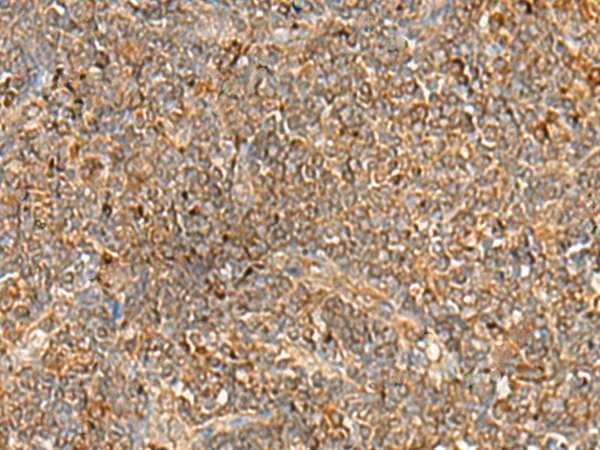

分类: 科研抗体货号: P09847别名:应用: IHC反应种属: Human